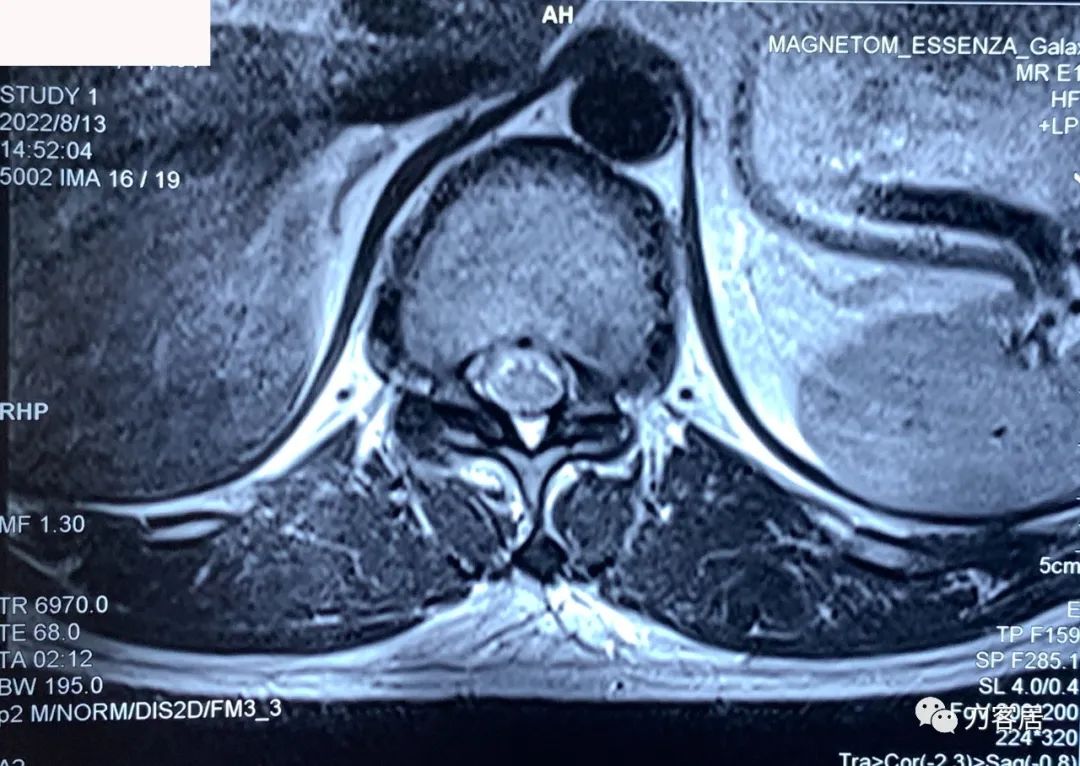

图7. 20220813西安第三方影像机构胸椎MRI01,提示胸8-9椎间盘突出,胸11-12椎间盘突出,椎管狭窄。

图8. 20220813西安第三方影像机构胸椎MRI02,提示胸8-9椎间盘突出,胸11-12椎间盘突出,椎管狭窄。

图9. 20220813西安第三方影像机构胸椎MRI03,脊髓水成像,显示胸11-12处脊髓受压。

图10. 20220813西安第三方影像机构胸椎MRI04,提示右侧隐窝狭窄,右侧黄韧带肥厚,但椎管狭窄并不那么严重。

图11. 20220813西安第三方影像机构胸椎MRI05,显示两侧胸椎黄韧带肥厚,右侧明显。但脊髓压迫似乎并不那么严重。

图12. 20220813西安第三方影像机构胸椎MRI06,显示两侧胸椎黄韧带肥厚,右侧明显。但脊髓压迫似乎并不那么严重。